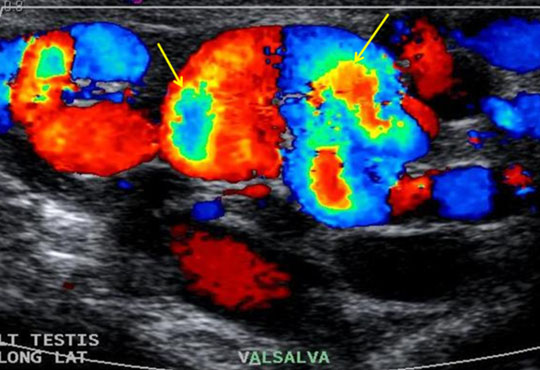

For assessment of size and appearance of both Testicles and associated structures (epidedymis, spermatic cord). To detect presence of inflammation or tumour, if any. Fluid collection in scrotal sac (Hydrocele). To rule out testicular torsion/ varicocele.